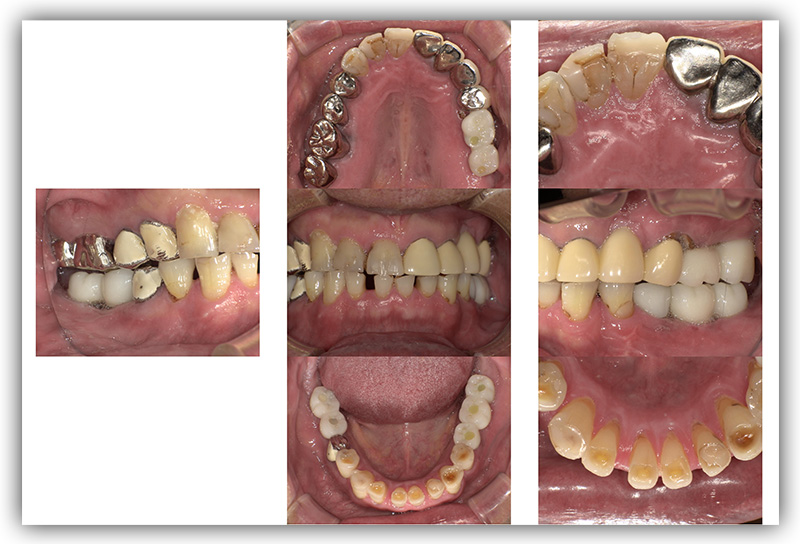

CASE_04

60代女性(インプラント)

- 患者さん情報(年齢・性別)

- 60代 女性

- 主訴

- 左下のインプラントを考えているが、怖い

- 治療箇所

- インプラント1箇所、セラミック3箇所

- 治療方法

- インプラント、セラミック治療

- 費用

- インプラント42.9万円、セラミック治療約24万円

- 治療期間

- 約1年6か月

- その治療によるリスク・副作用

-

- 保険が効かない

- 外科的治療が必要

- 患者様の声